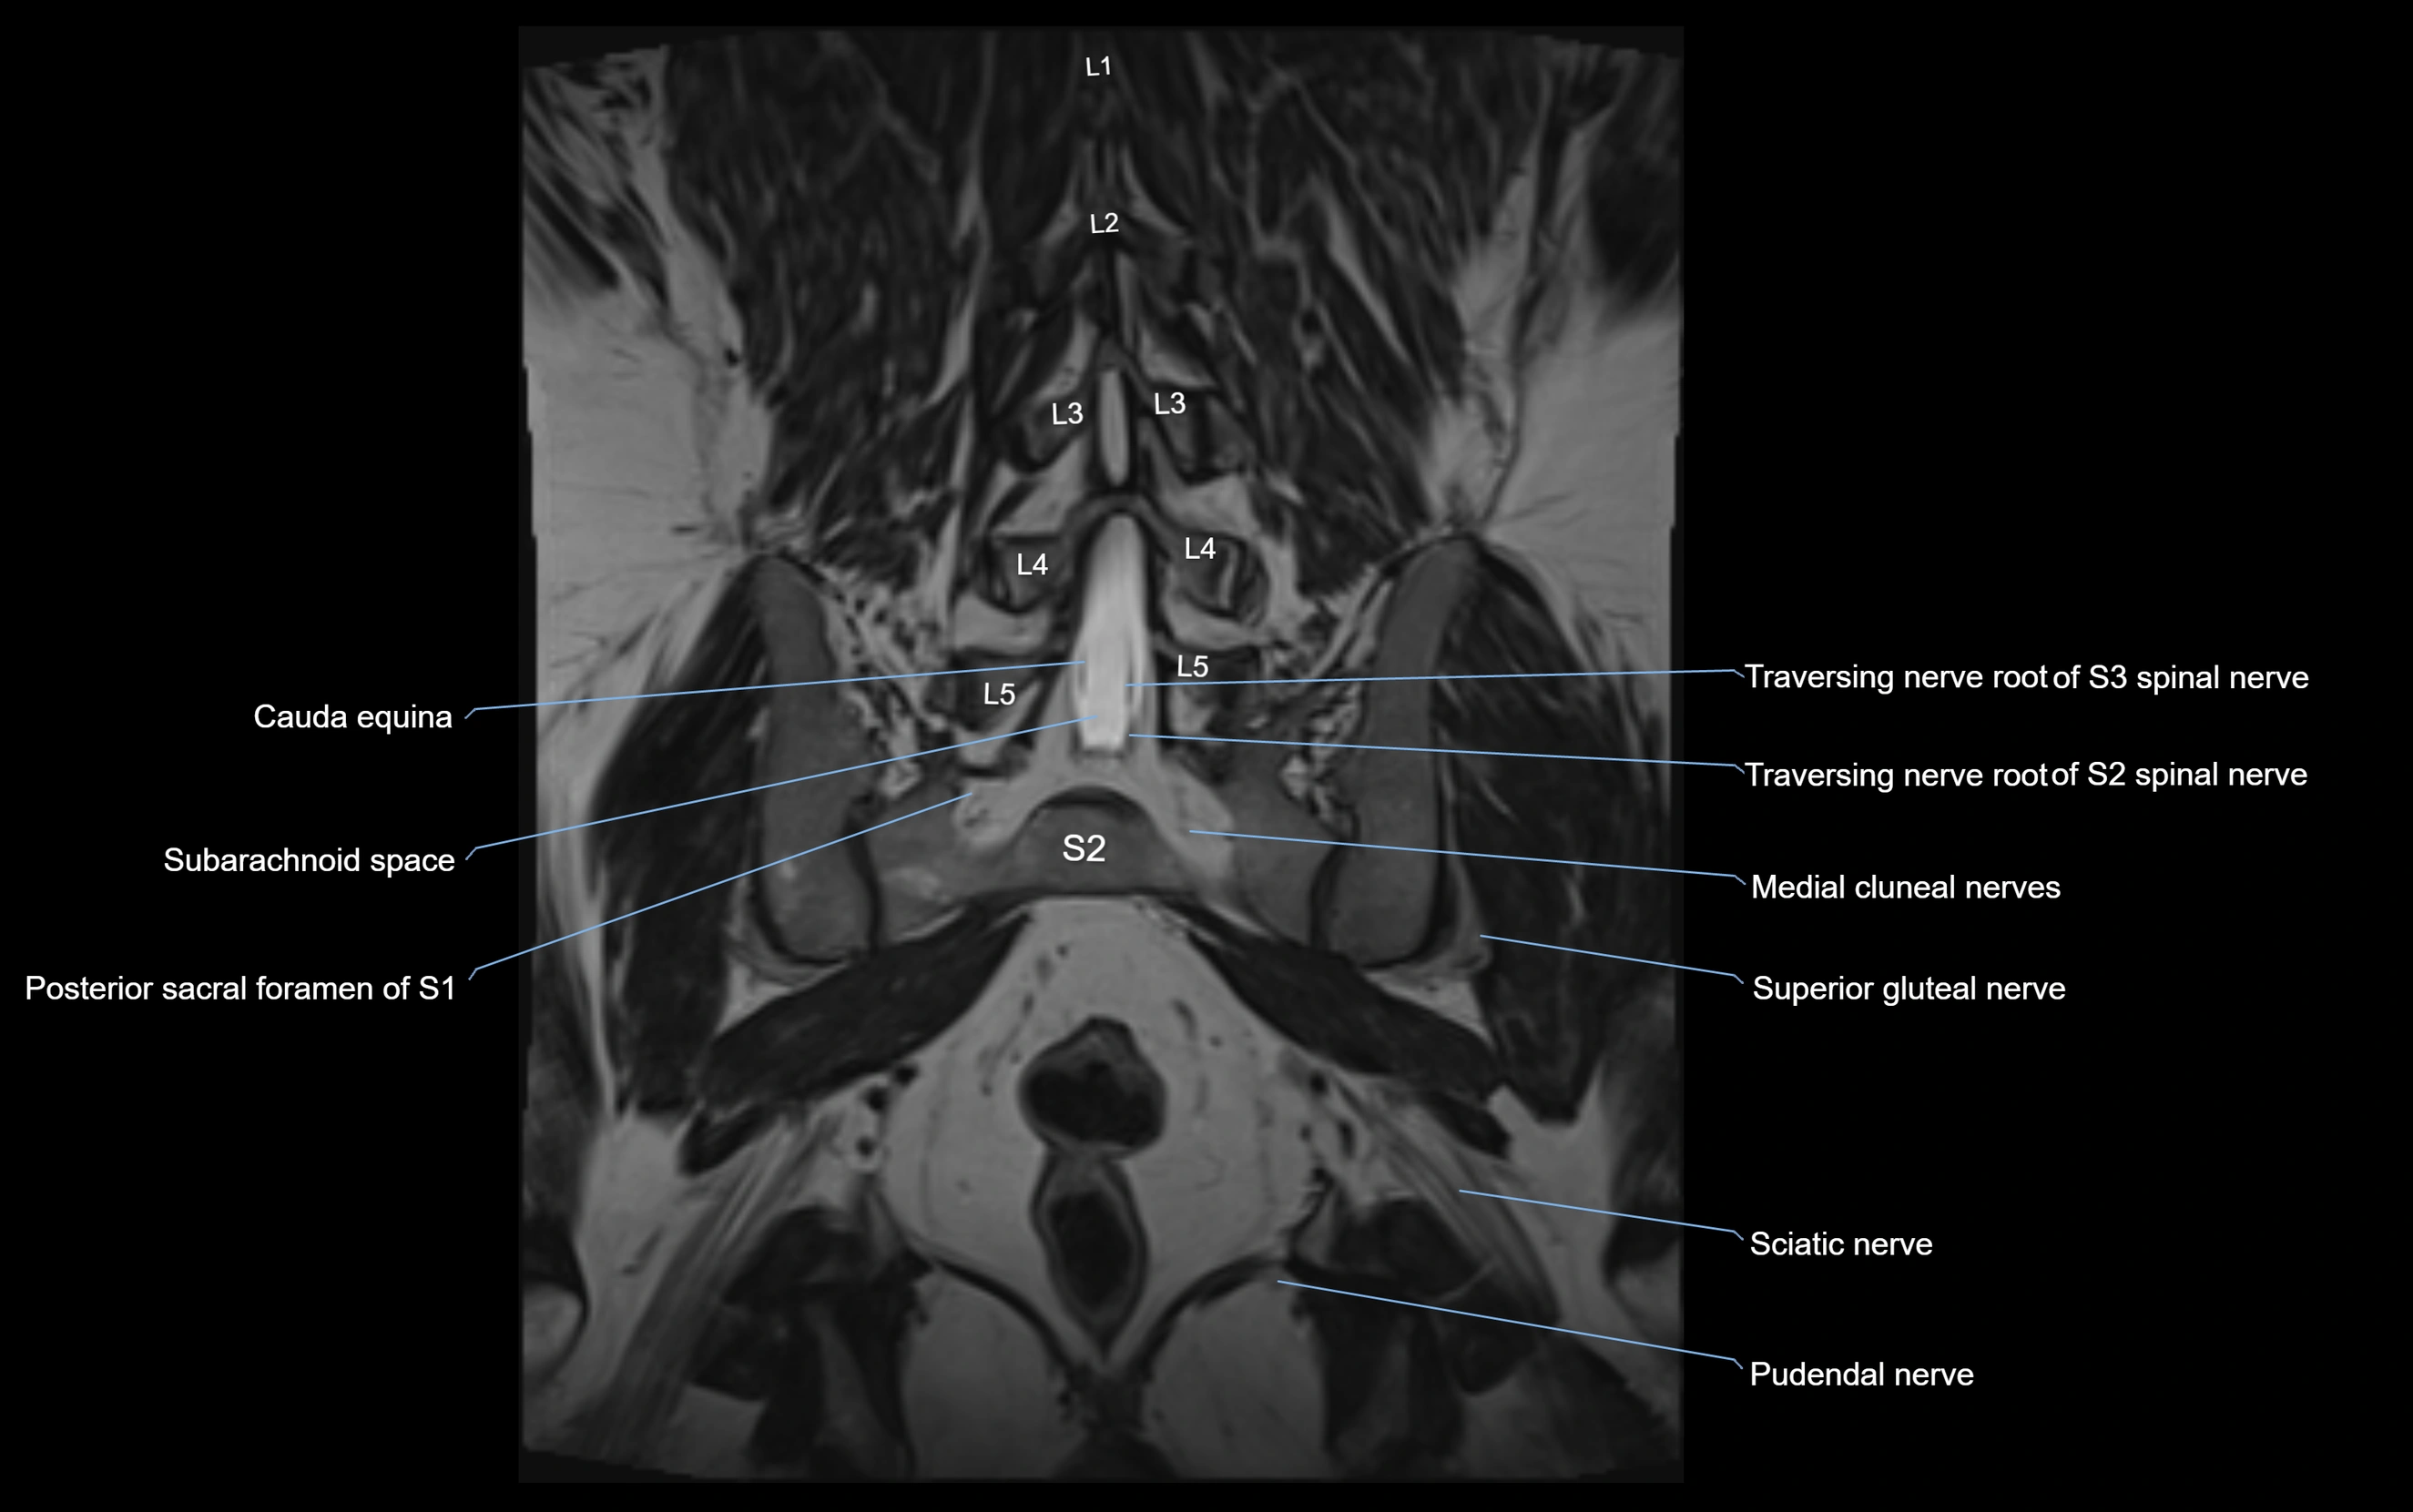

MRI image

image